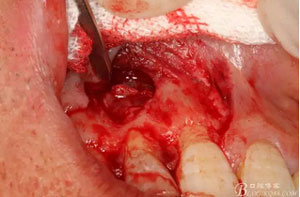

圖8.從垂直切口和水平切口的連接處翻瓣。發(fā)現(xiàn)11和12之間的骨壁有缺損。

圖9.翻開角形瓣后,有骨壁缺損,囊壁有穿孔,這就是溢膿的竇道出口。